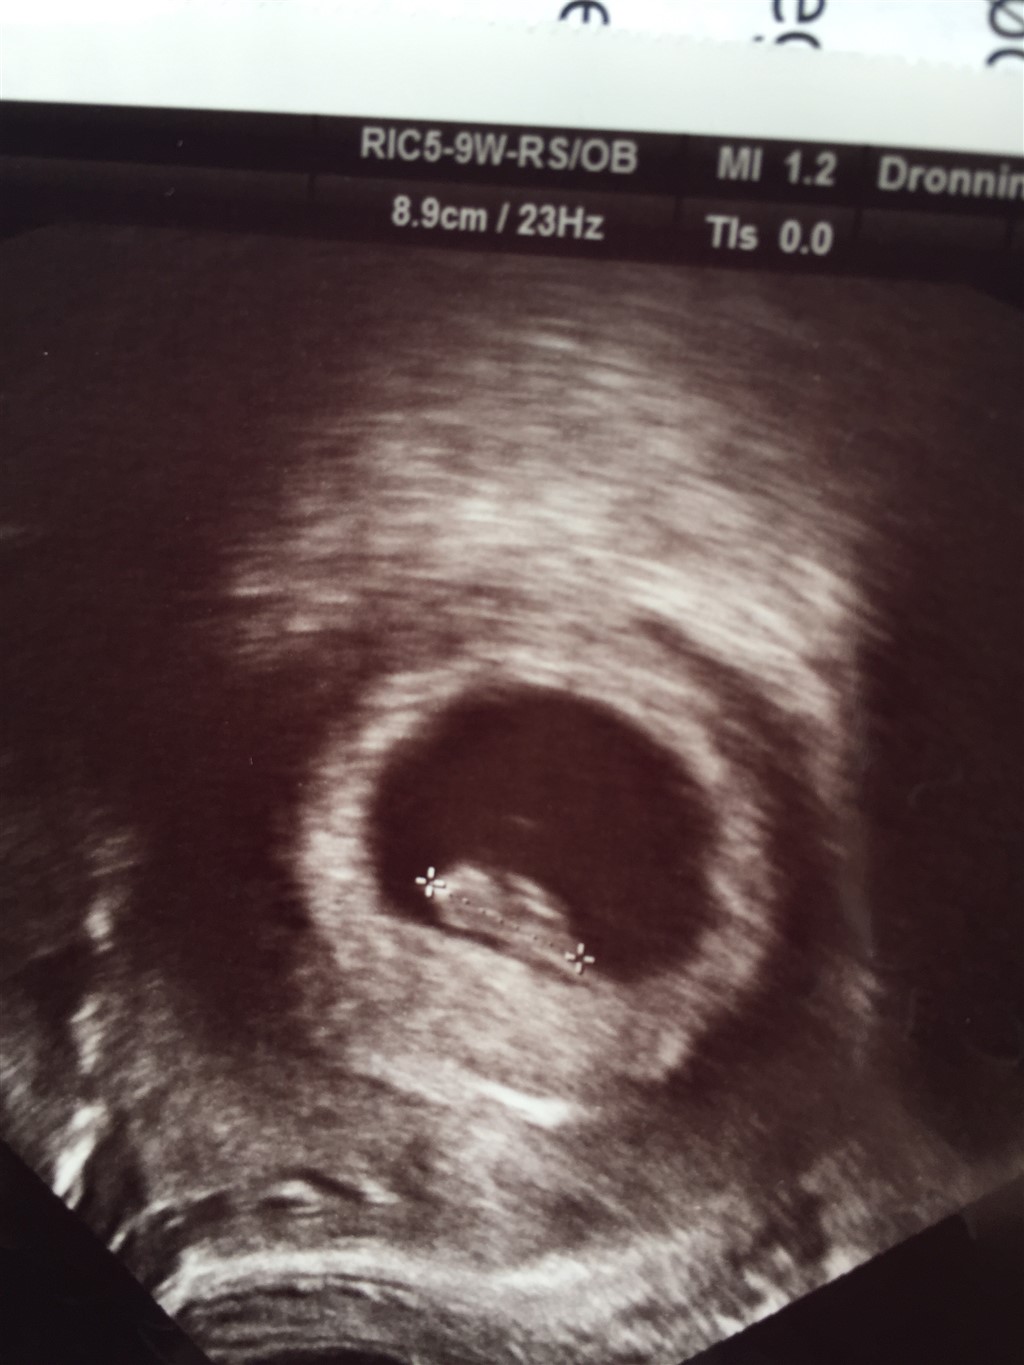

Nå tøser TS var overstået 12.05

for det første har jeg en cyste på venstre æggestok (den der er skyld i mine smerter)

også er der en lille spunk på 12.1mm i livmoder med hjerteblink som forventes at ankomme 20/3-16

blev rykket 2 dage tilbage så er 7+3 i dag

er så lettet og har haft min tudetur af glæde

Vedhæftede fotos (klik for at se i fuld størrelse)